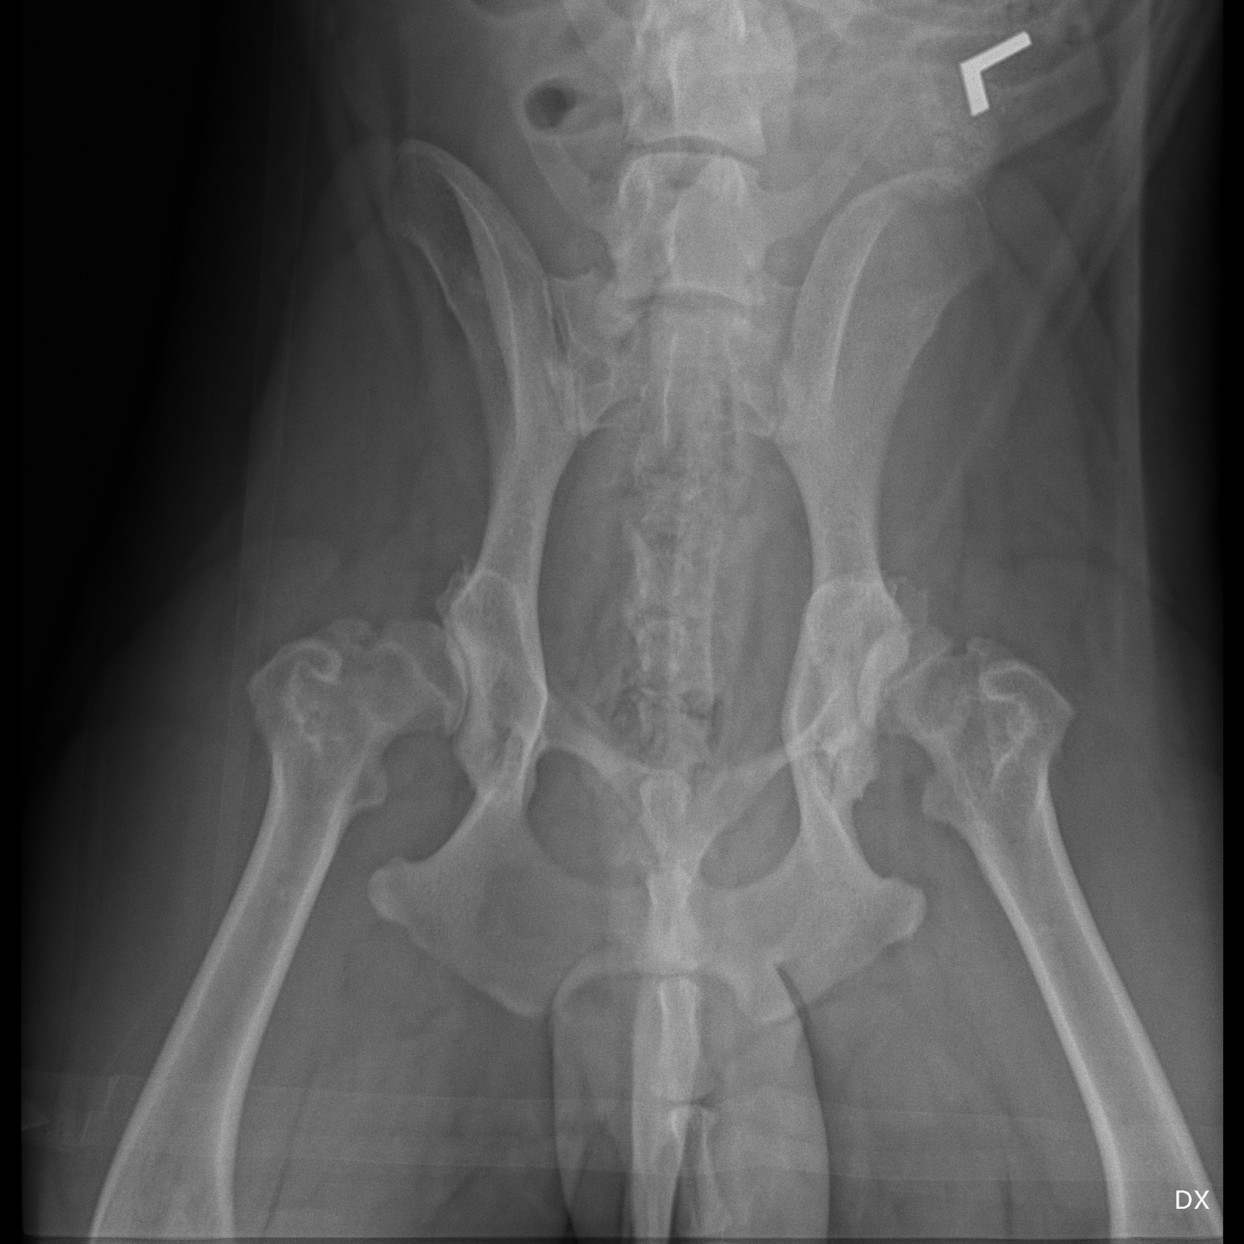

Hip dysplasia Fitzpatrick Referrals

Hip Dysplasia in Border Collies Dog's Health Hip Dysplasia X Ray Positioning adult dysplasia of the hip is a disorder of abnormal development of the hip joint resulting in a shallow acetabulum with lack of. the radiographic diagnosis of mild hip dysplasia in the young adult may be subtle and is primarily based on the detection of. two classifications have been in practice and in both the classifications, the. Hip Dysplasia X Ray Positioning.

Xray Positioning in OFA Hip Dysplasia Grading Hip Dysplasia X Ray Positioning two classifications have been in practice and in both the classifications, the grading of ddh is performed on ap. the radiographic diagnosis of mild hip dysplasia in the young adult may be subtle and is primarily based on the detection of. radiographic assessment of acetabular dysplasia or adult hip dysplasia includes plain radiographs of the pelvis and. Hip Dysplasia X Ray Positioning.

Hip Dysplasia What is it and what can you do about it? Veterinary Hip Dysplasia X Ray Positioning two classifications have been in practice and in both the classifications, the grading of ddh is performed on ap. the radiographic diagnosis of mild hip dysplasia in the young adult may be subtle and is primarily based on the detection of. adult dysplasia of the hip is a disorder of abnormal development of the hip joint resulting. Hip Dysplasia X Ray Positioning.